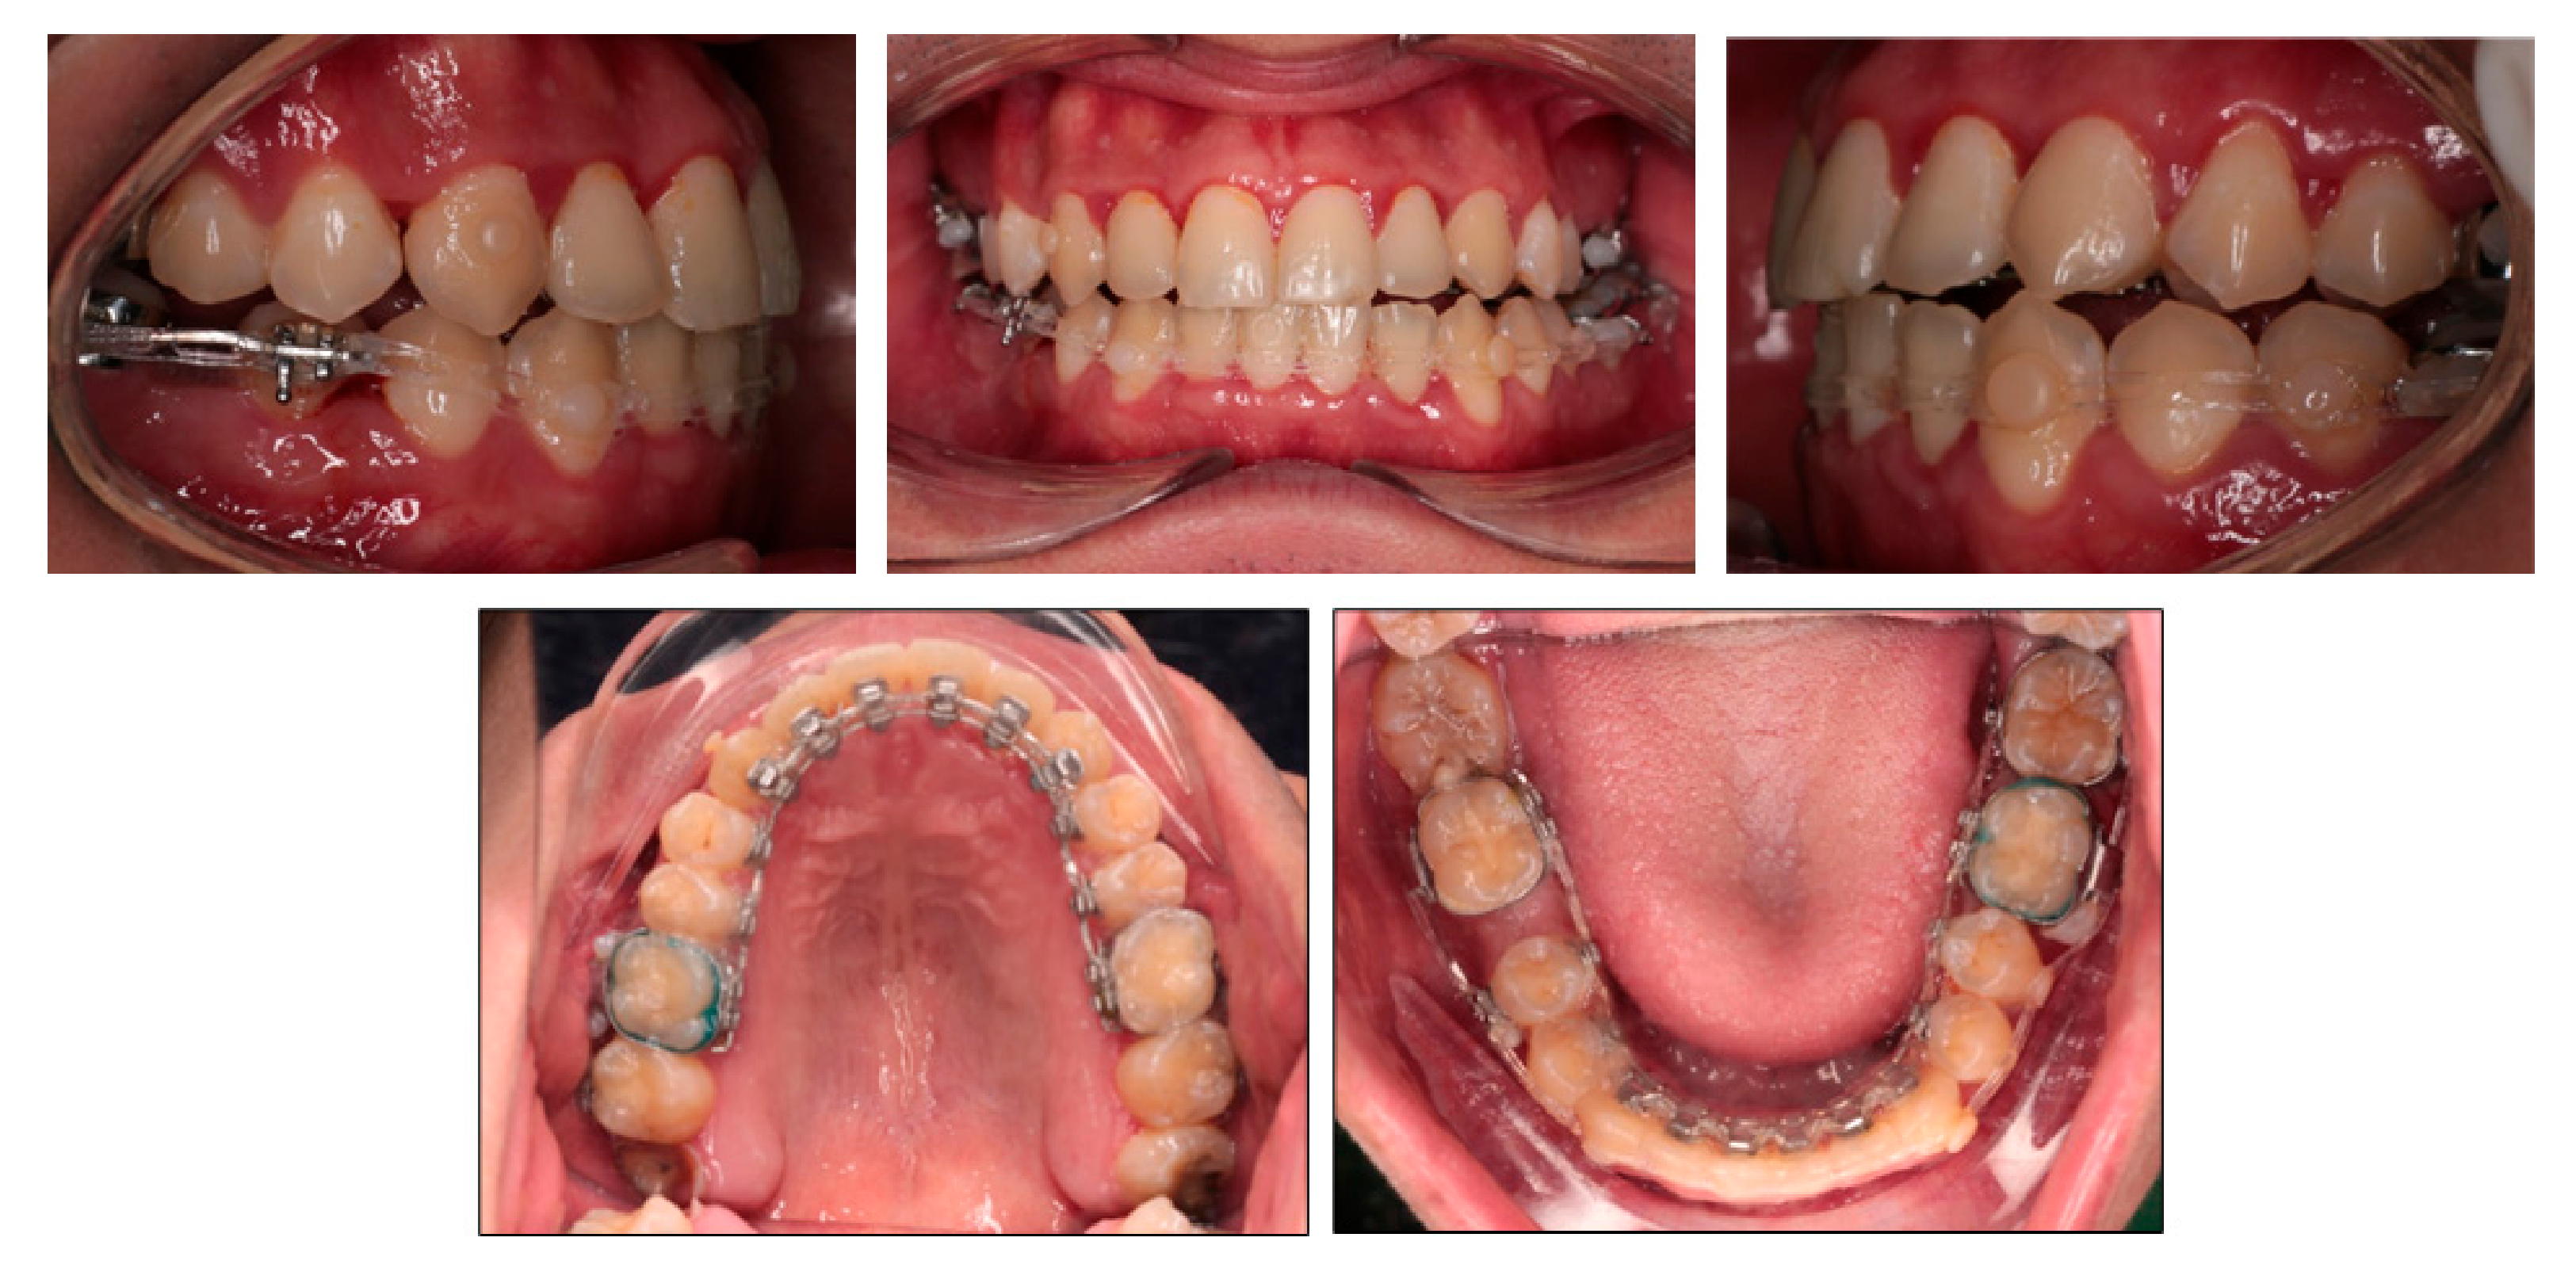

After 15 months of treatment, the positive overbite and overjet were obtained (Figure 5). The lateral openbite on both sides was almost corrected with only 1 mm of open bite remaining. The lower midline deviation was significantly improved. The mandibular left second molar extraction space was completely closed, and the mandibular right first molar extraction space was closed by two thirds. A V-bend was applied to the labial segmental archwire in the lower right quadrant in order to bring upright the mandibular right second molar. The buccal crossbite on the left side became edge-to-edge bite. On the right side, the transverse buccal interdigitation was still not normal with lingually placed mandibular premolars and buccally placed maxillary premolars. Canine relationship was Class II in the left side.

Figure 5.

15-month treatment follow-up photographs.